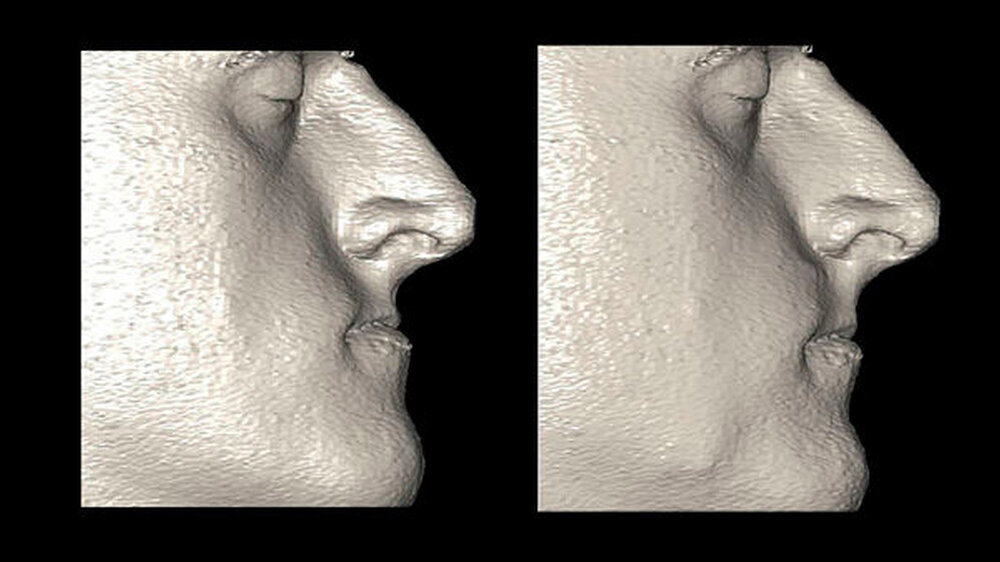

Gesichtsscanner: Hochtechnologie für mehr Patientensicherheit

Künftig kann das postoperative Ergebnis mittels eines Gesichtsscanners der neuesten Generation noch besser für den Patienten vorhersagbar werden. Hochtechnologie für genauere Vorhersagbarkeit des OP-Ergebnisses und damit gesteigerte Patientensicherheit. Da es sich hierbei um ein ganz neues Verfahren handelt, stehen Langzeituntersuchungen und -auswertungen noch aus.